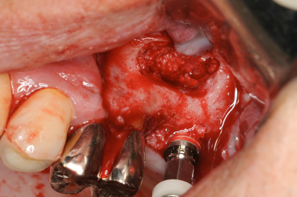

4ヶ月後の患部、もう一度サイナスリフトをアプローチ

4ヶ月経つとこのように前回骨を削ったところもこのようにきれいに再生しています。粘膜も一度触っているので再生してことによって厚みがでて、剥離もしやすくなっています。

人工骨に再生医療で使われるCGFを混ぜています。採血管をプラスチックにすることによりCGFが液体状になり、人工骨と混ぜやすくなります。